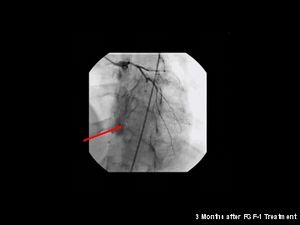

Neo-angiogenesis in a woman's heart after FGF-1 treatment

حدد الباحثون بمتشفى كليفلند (Cleveland Clinic) في دراسة تمت سنة 2006،منطقة في كروموسوم 17 مختصة بالعائلات التي تصاب بعدة حالات من الجلطة القلبية(myocardial infarction). كما يوجد خلاف حول العلاقة بين الإصابة بمرض تصلب الأوعية الدموية (atherosclerosis) والعدوى بالبكتيريا Chlamydophila pneumoniae،بينما أُثبت وجود هذه البكتيريا الذي تعيش داخل الخلية في صفيحة الكولسترول لدى المرضى المصابين بتصلب الأوعية، فما زالت هذه البراهين غير حاسمة فيما إن كانت هذه البكتيريا بحد ذاتها عامل مسبب للمرض. لم يظهر العلاج بالمضادات الحيوية (antibiotics) لمرضى تصلب الأوعية الدموية أي تقليل لخطر الإصابة بالنوبة القلبية (heart attacks) أو أمراض الأوعية التاجية الأخرى. منذ سنة 1990 والبحث جاري نحو خيارات جديدة للعلاج لأمراض أوعية القلب التاجية تُركز على استخدام ما يسمى تكوّن الأوعية الدمويةangiogenesis والخلايا الجذعية stem cell. حيث أجريت الكثير من التجارب السريرية إما بتطبيق العلاج ببروتين عامل النمو لتكوّن الأوعية الدموية (angiogenic growth factor) مثل: FGF-1 أو VEGF ،أو العلاج بالخلايا باستخدام أنواع مختلفة من الخلايا الجذعية. وما زالت الأبحاث قائمة توعد بمستقبل مشرق للعلاج خصوصا فيما يتعلق ب FGF-1 والانتفاع الخلايا المُولدّة للخلايا المبطّنة للأوعية الدموية endothelial) progenitor cells).